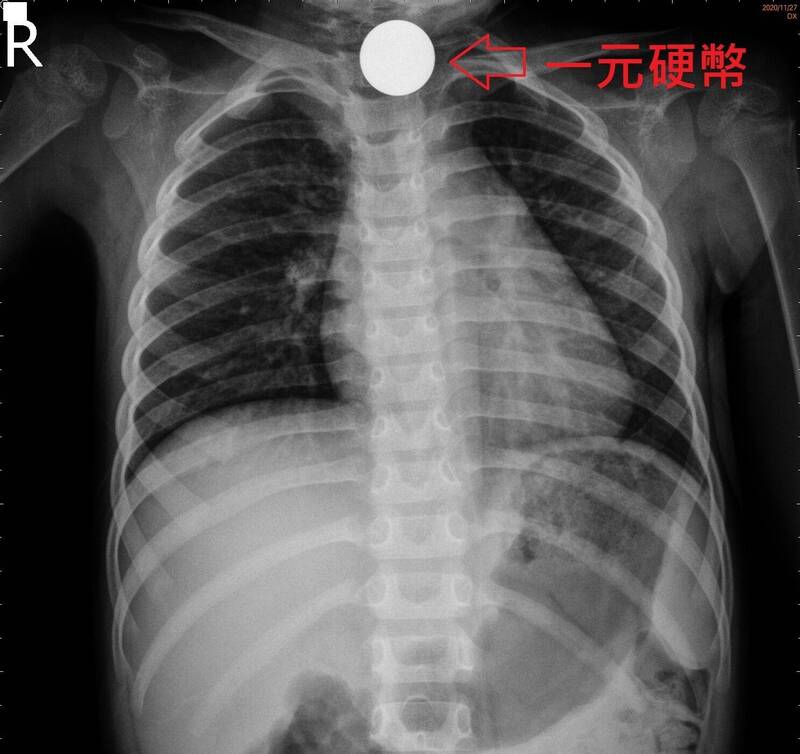

宜蘭縣薛小妹誤吞2枚1元硬幣,主治醫師即刻救援,10分鐘順利取出,圖為示意畫面。(記者江志雄攝

事發後,薛小妹妹大聲哭鬧,由媽媽送到羅東聖母醫院掛急診,照X光發現硬幣卡在頸部食道下不去,值班的腸胃科醫師王威迪評估後,排除傳統處理方式,改採比較快速的胃鏡夾除術,女童不用麻醉,坐著母親胸前,四肢包裹固定,張開嘴巴,不久後夾出硬幣。

X光片畫面顯示,薛小妹吞下的硬幣卡在食道。(記者江志雄翻攝)